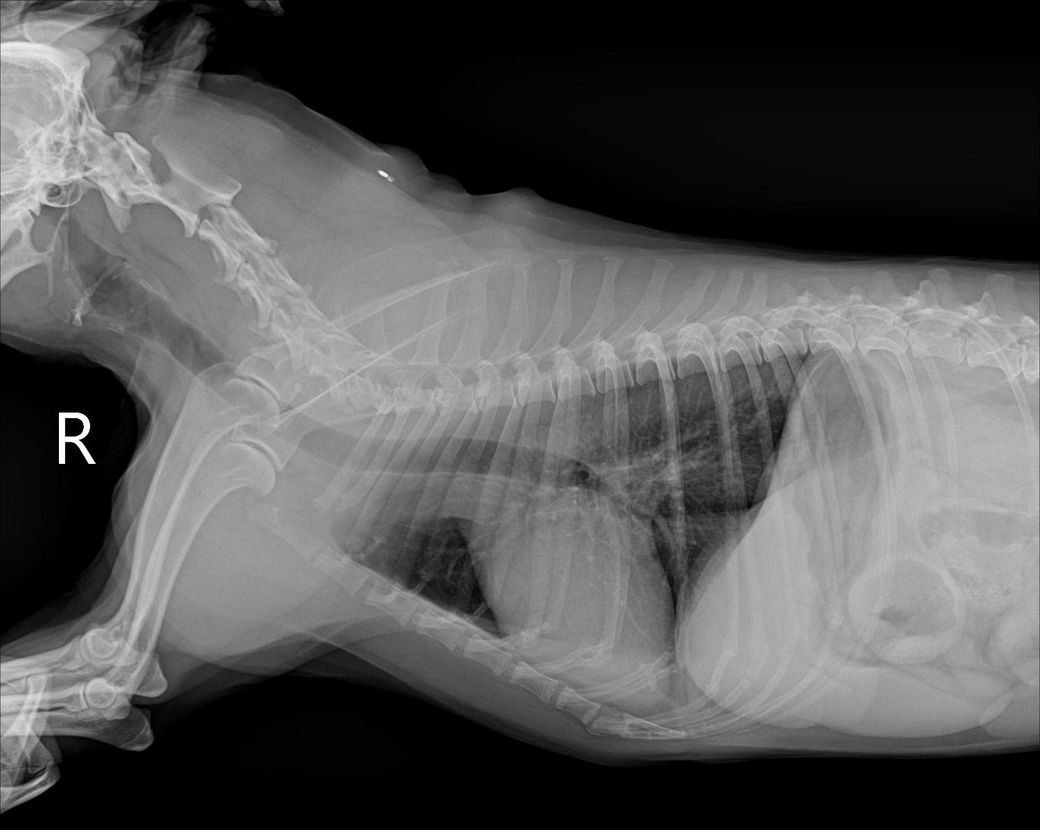

간크기 작다고 하는데 어디를봐야 작은걸 알수있을까요?? 정말 간이 작은 편인건도 궁금합니다!!

믹스(중성화o), 몸무게9.3kg 입니다